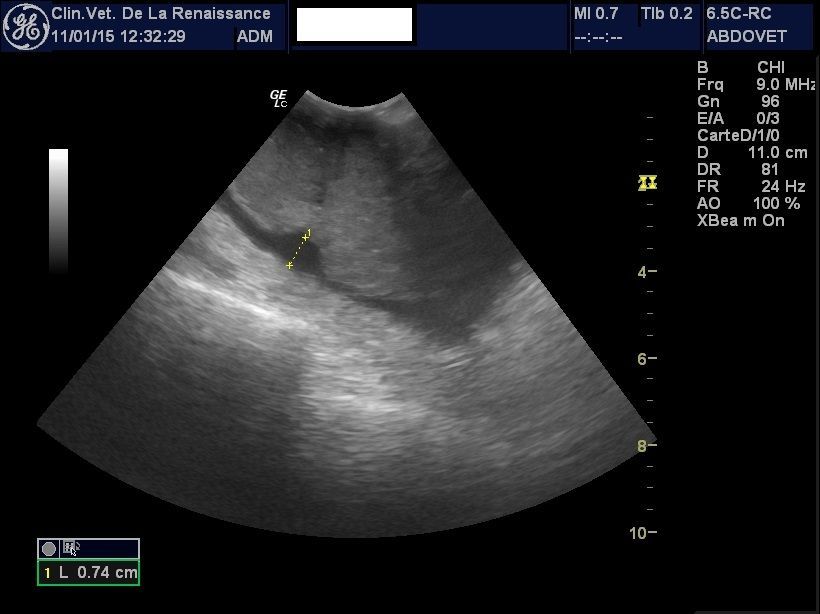

L'échographie

La clinique est équipée d'un échographe pour l'exploration de la cavité abdominale et de ses organes. Nous pouvons réaliser une échographie ciblée sur un organe ou sur l'ensemble des organes abdominaux, dans le cadre d'un diagnostic ou le suivi d'une pathologie ou d'une gestation. Un doppler permet dans le cadre de la gestation de mesurer la fréquence cardiaque des chiots. L'échographie peut être réalisée avec ou sans anesthésie générale en fonction de l'animal.